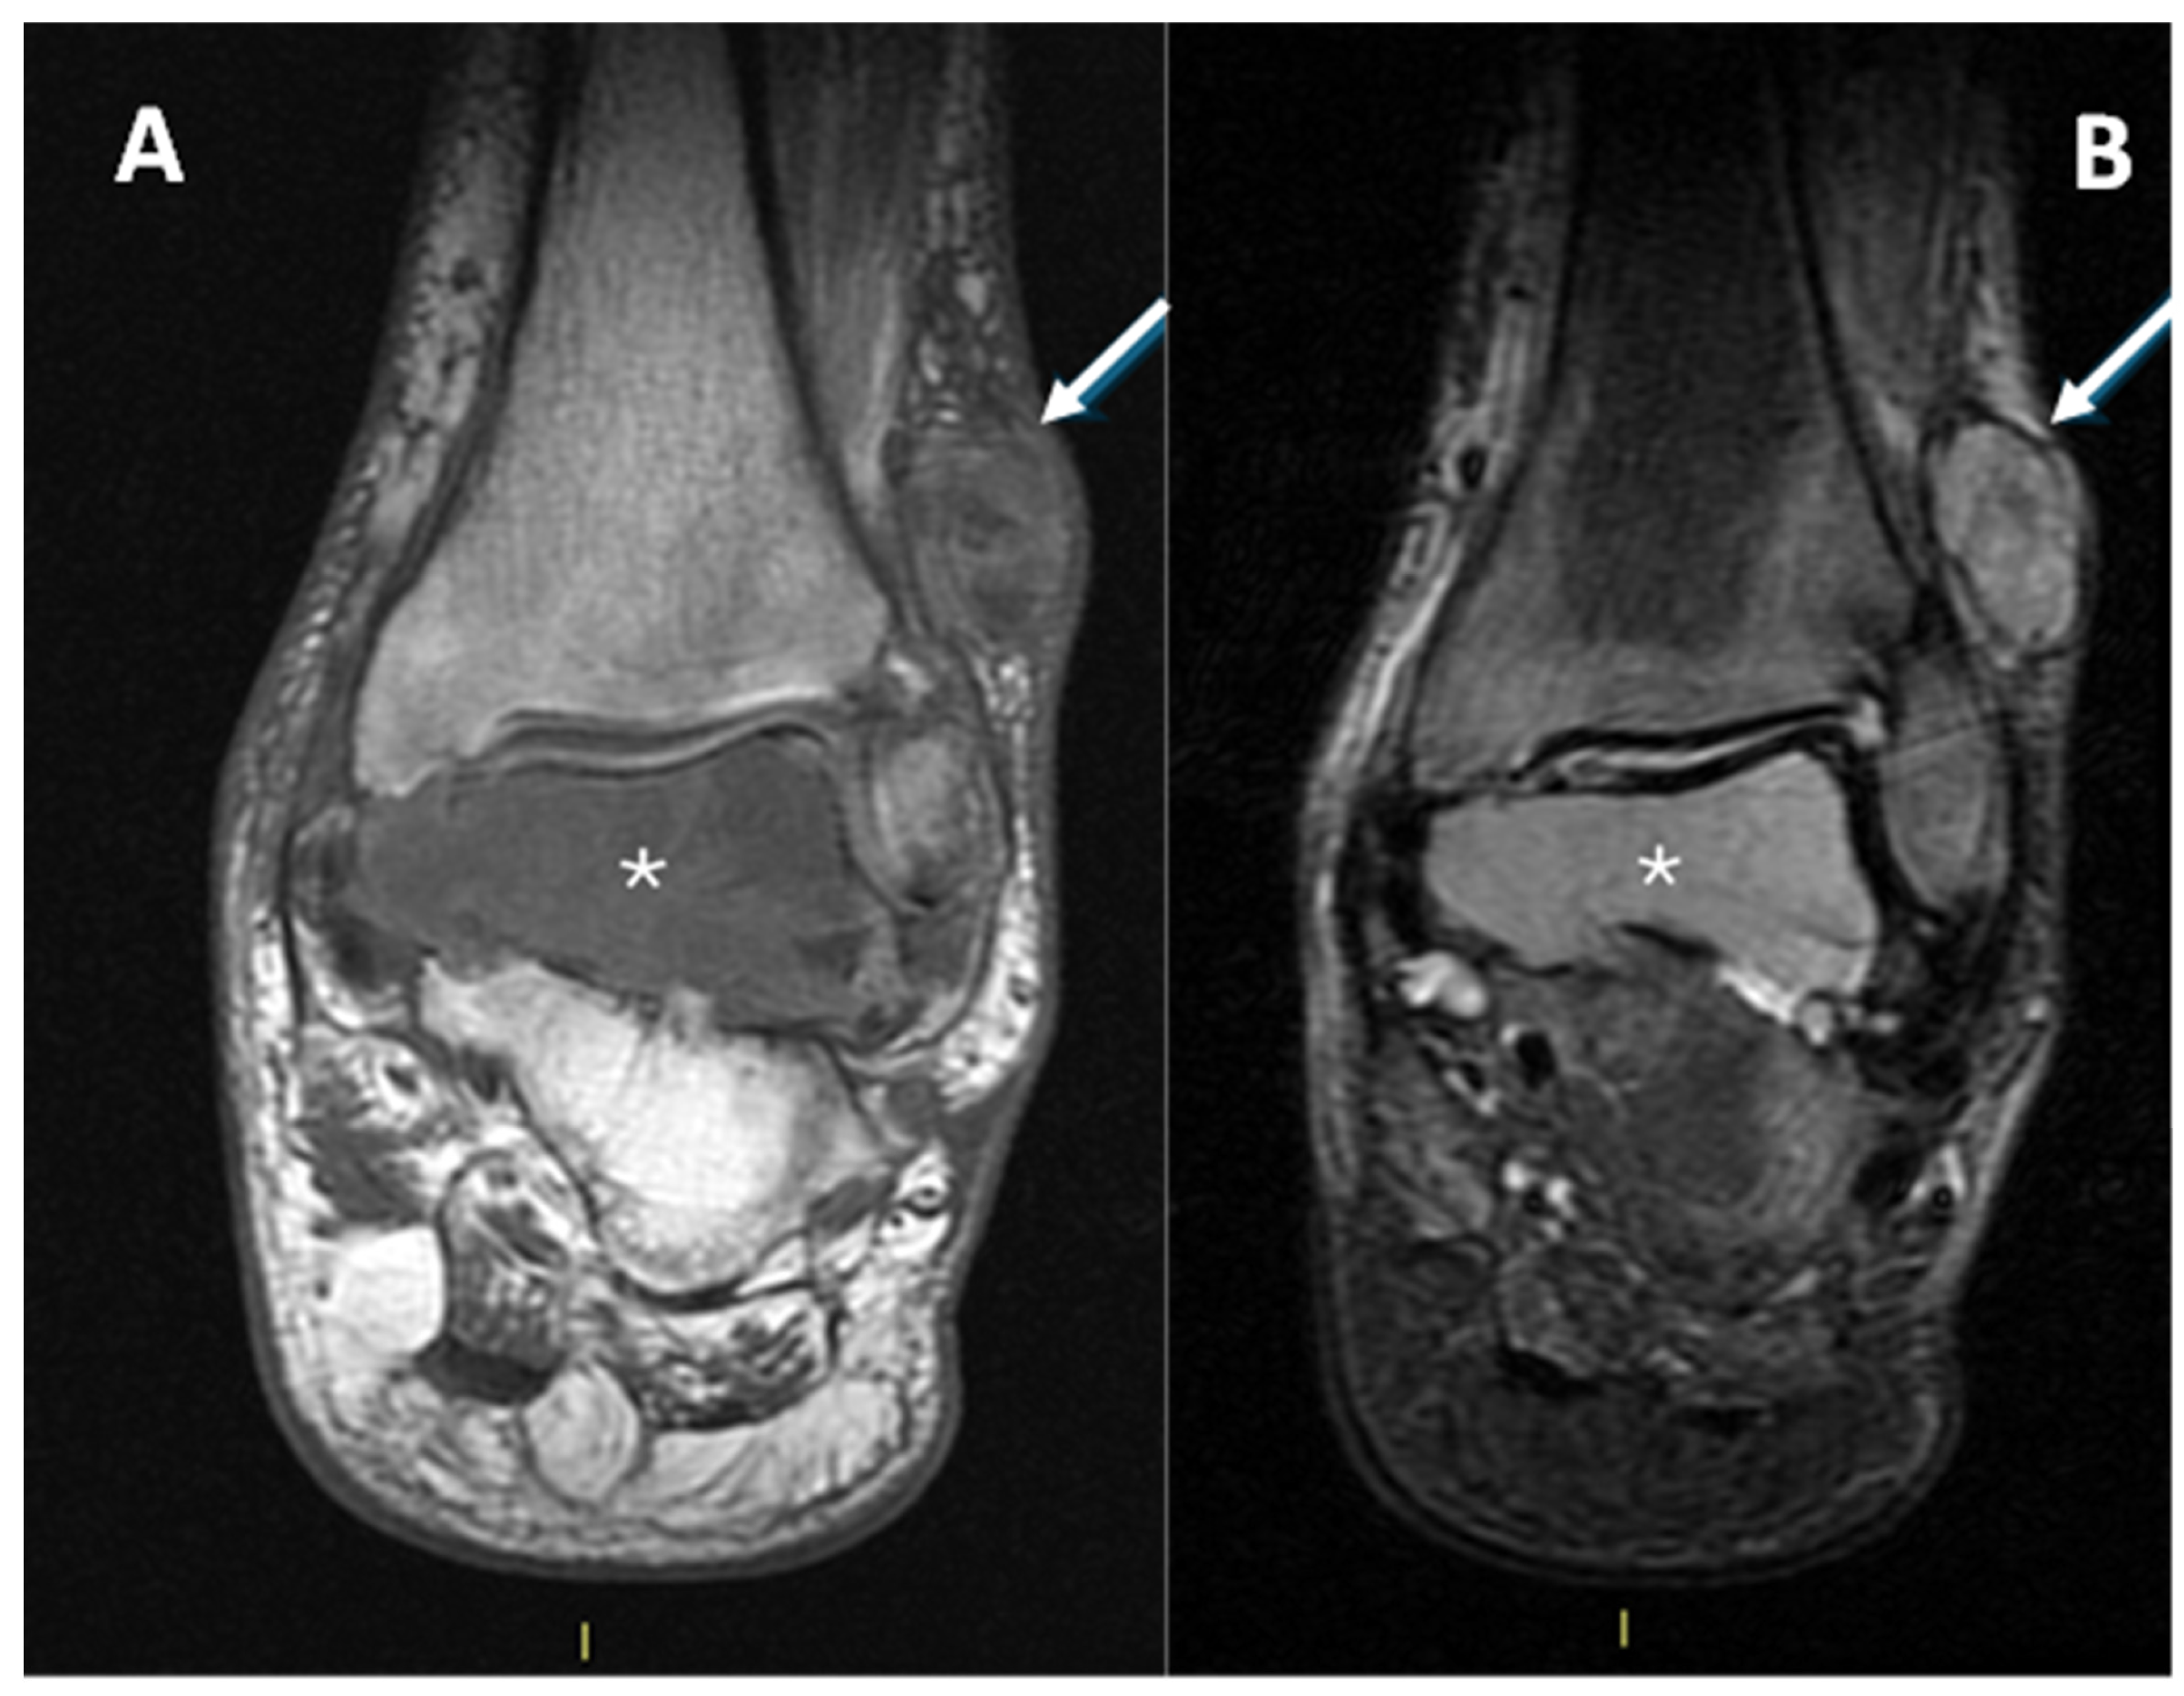

3.4. MRI Features

3.4.1. General MRI Features

3.4.2. Peritumoral Edema

3.4.3. Other MRI Features